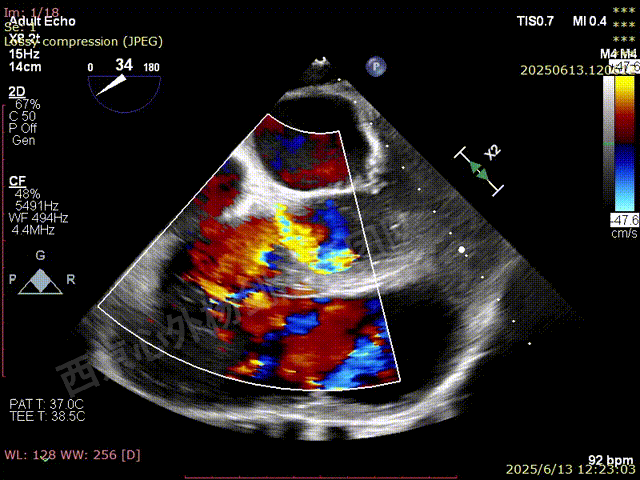

TAVR术后,全心增大,二尖瓣反流重度,三尖瓣反流重度。中量心包积液。左室严重增大,标准图像调整困难。主动脉瓣位带支架人工瓣膜瓣叶启闭正常,主动脉瓣位人工瓣上血流速度Vmax 148cm/s,PGmax 9mmHg,Vmean 86cm/s,PGmean 2mmHg, VTI 34.7cm,瓣周反流(轻)。估测肺动脉收缩压约49mmHg;左室收缩功能明显减低。LVEF:23%,EDV:364ml,ESV:221ml。

彩色血流示:二尖瓣反流缩流颈彩宽6.6mm,面积17cm²,容积30ml;二尖瓣瓣口面积6.6cm²,瓣环内径:左右径34mm,前后径34mm。2区瓣叶长度:前叶36mm,后叶20mm,叶环比1.6. 三尖反流面积17.2cm²,容积33ml,Vmax 291cm/s,PGmax 34mmHg。